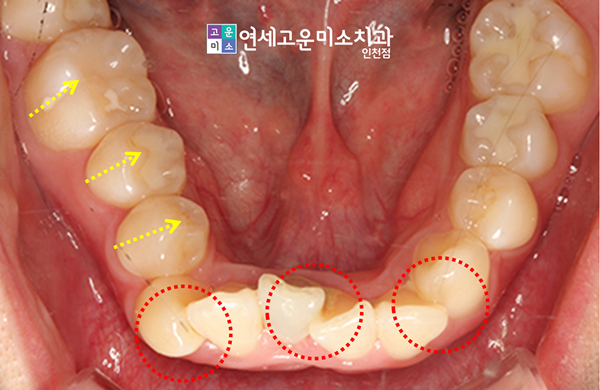

지금부터 소개할 환자분께서는 치아의 배열이 심각하게 비뚤어져 있다고 하셨습니다.

전체적으로 총생이 심해서 덧니교정이 필요해 보였는데요. 상악 앞니가 겹쳐져 있고, 이곳의 측절치가 거꾸로 물린 반대교합이 관찰되었습니다.

윗니와 아랫니의 배열이 전부 심하게 틀어진 것으로 보이며, 이로 인해 중심선이 제대로 일치하지 않는 모습이었습니다.

잇몸의 경계선도 전체적으로 균일하지 못한 편이었습니다.

무엇보다 오른쪽의 측면교합이 상당히 좋지 않았습니다. 아래쪽 송곳니가 내려와 있고, 이외에 나머지 어금니들이 같은 라인에서 닿아 있었는데요.

우측 구치부에서 윗니가 약간 아랫니를 깊게 무는 듯한 느낌도 적지 않게 받았습니다.

전체적으로 상하교합에 있어 치주조직이 감당할 부담도 상당할 것이라고 예상됐습니다.

이로 인해 해당 부위 치아의 각도가 안쪽으로 기울어버리는 설측경사가 나타났습니다.